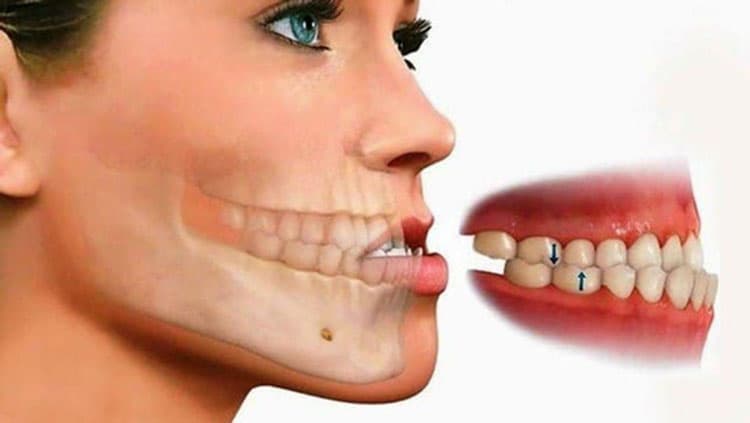

Hô móm do xương hàm

Nếu răng hô móm do nguyên nhân chính từ cấu trúc xương hàm, vấn đề này thường phức tạp hơn và yêu cầu can thiệp chuyên sâu. Hô móm do xương hàm là tình trạng cấu trúc xương hàm trên hoặc xương hàm dưới phát triển quá mức hoặc quá ít gây nên tình trạng hô hoặc móm. Hàm trên có thể nhô ra ngoài (hô) hoặc hàm dưới phát triển quá mức (móm). Dấu hiệu rõ rệt là khuôn mặt mất cân đối, với một hàm nhô ra ngoài so với hàm còn lại.

Điều này có thể làm khó khăn trong việc nhai thức ăn và gây đau ở khớp thái dương hàm. Trong trường hợp này, niềng răng đơn thuần không thể giải quyết được vấn đề, cần phải kết hợp với phẫu thuật để điều chỉnh lại cấu trúc xương hàm.